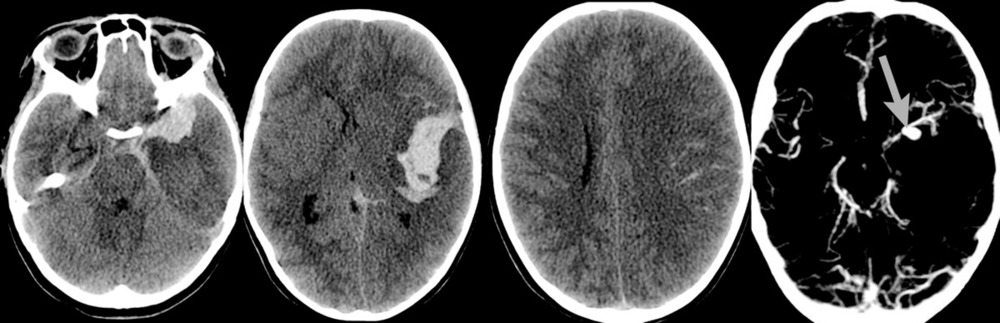

При поступлении на 2-е сутки после аСАК девочка находилась в коматозном состоянии: 4 балла по шкале комы Глазго. При неврологическом осмотре выявлялись мидриаз (D=S) и отсутствие фотореакции. В ответ на болевой стимул отмечались реакции по типу децеребрации. По данным компьютерной томографии (КТ) и КТ-ангиографии головного мозга были выявлены: аневризма левой СМА, субарахноидально-паренхиматозное кровоизлияние с формированием гематомы объемом около 30 см3 в области левой сильвиевой щели, латеральная дислокация срединных структур 6,5 мм, сдавление охватывающей цистерны (рис. 1).